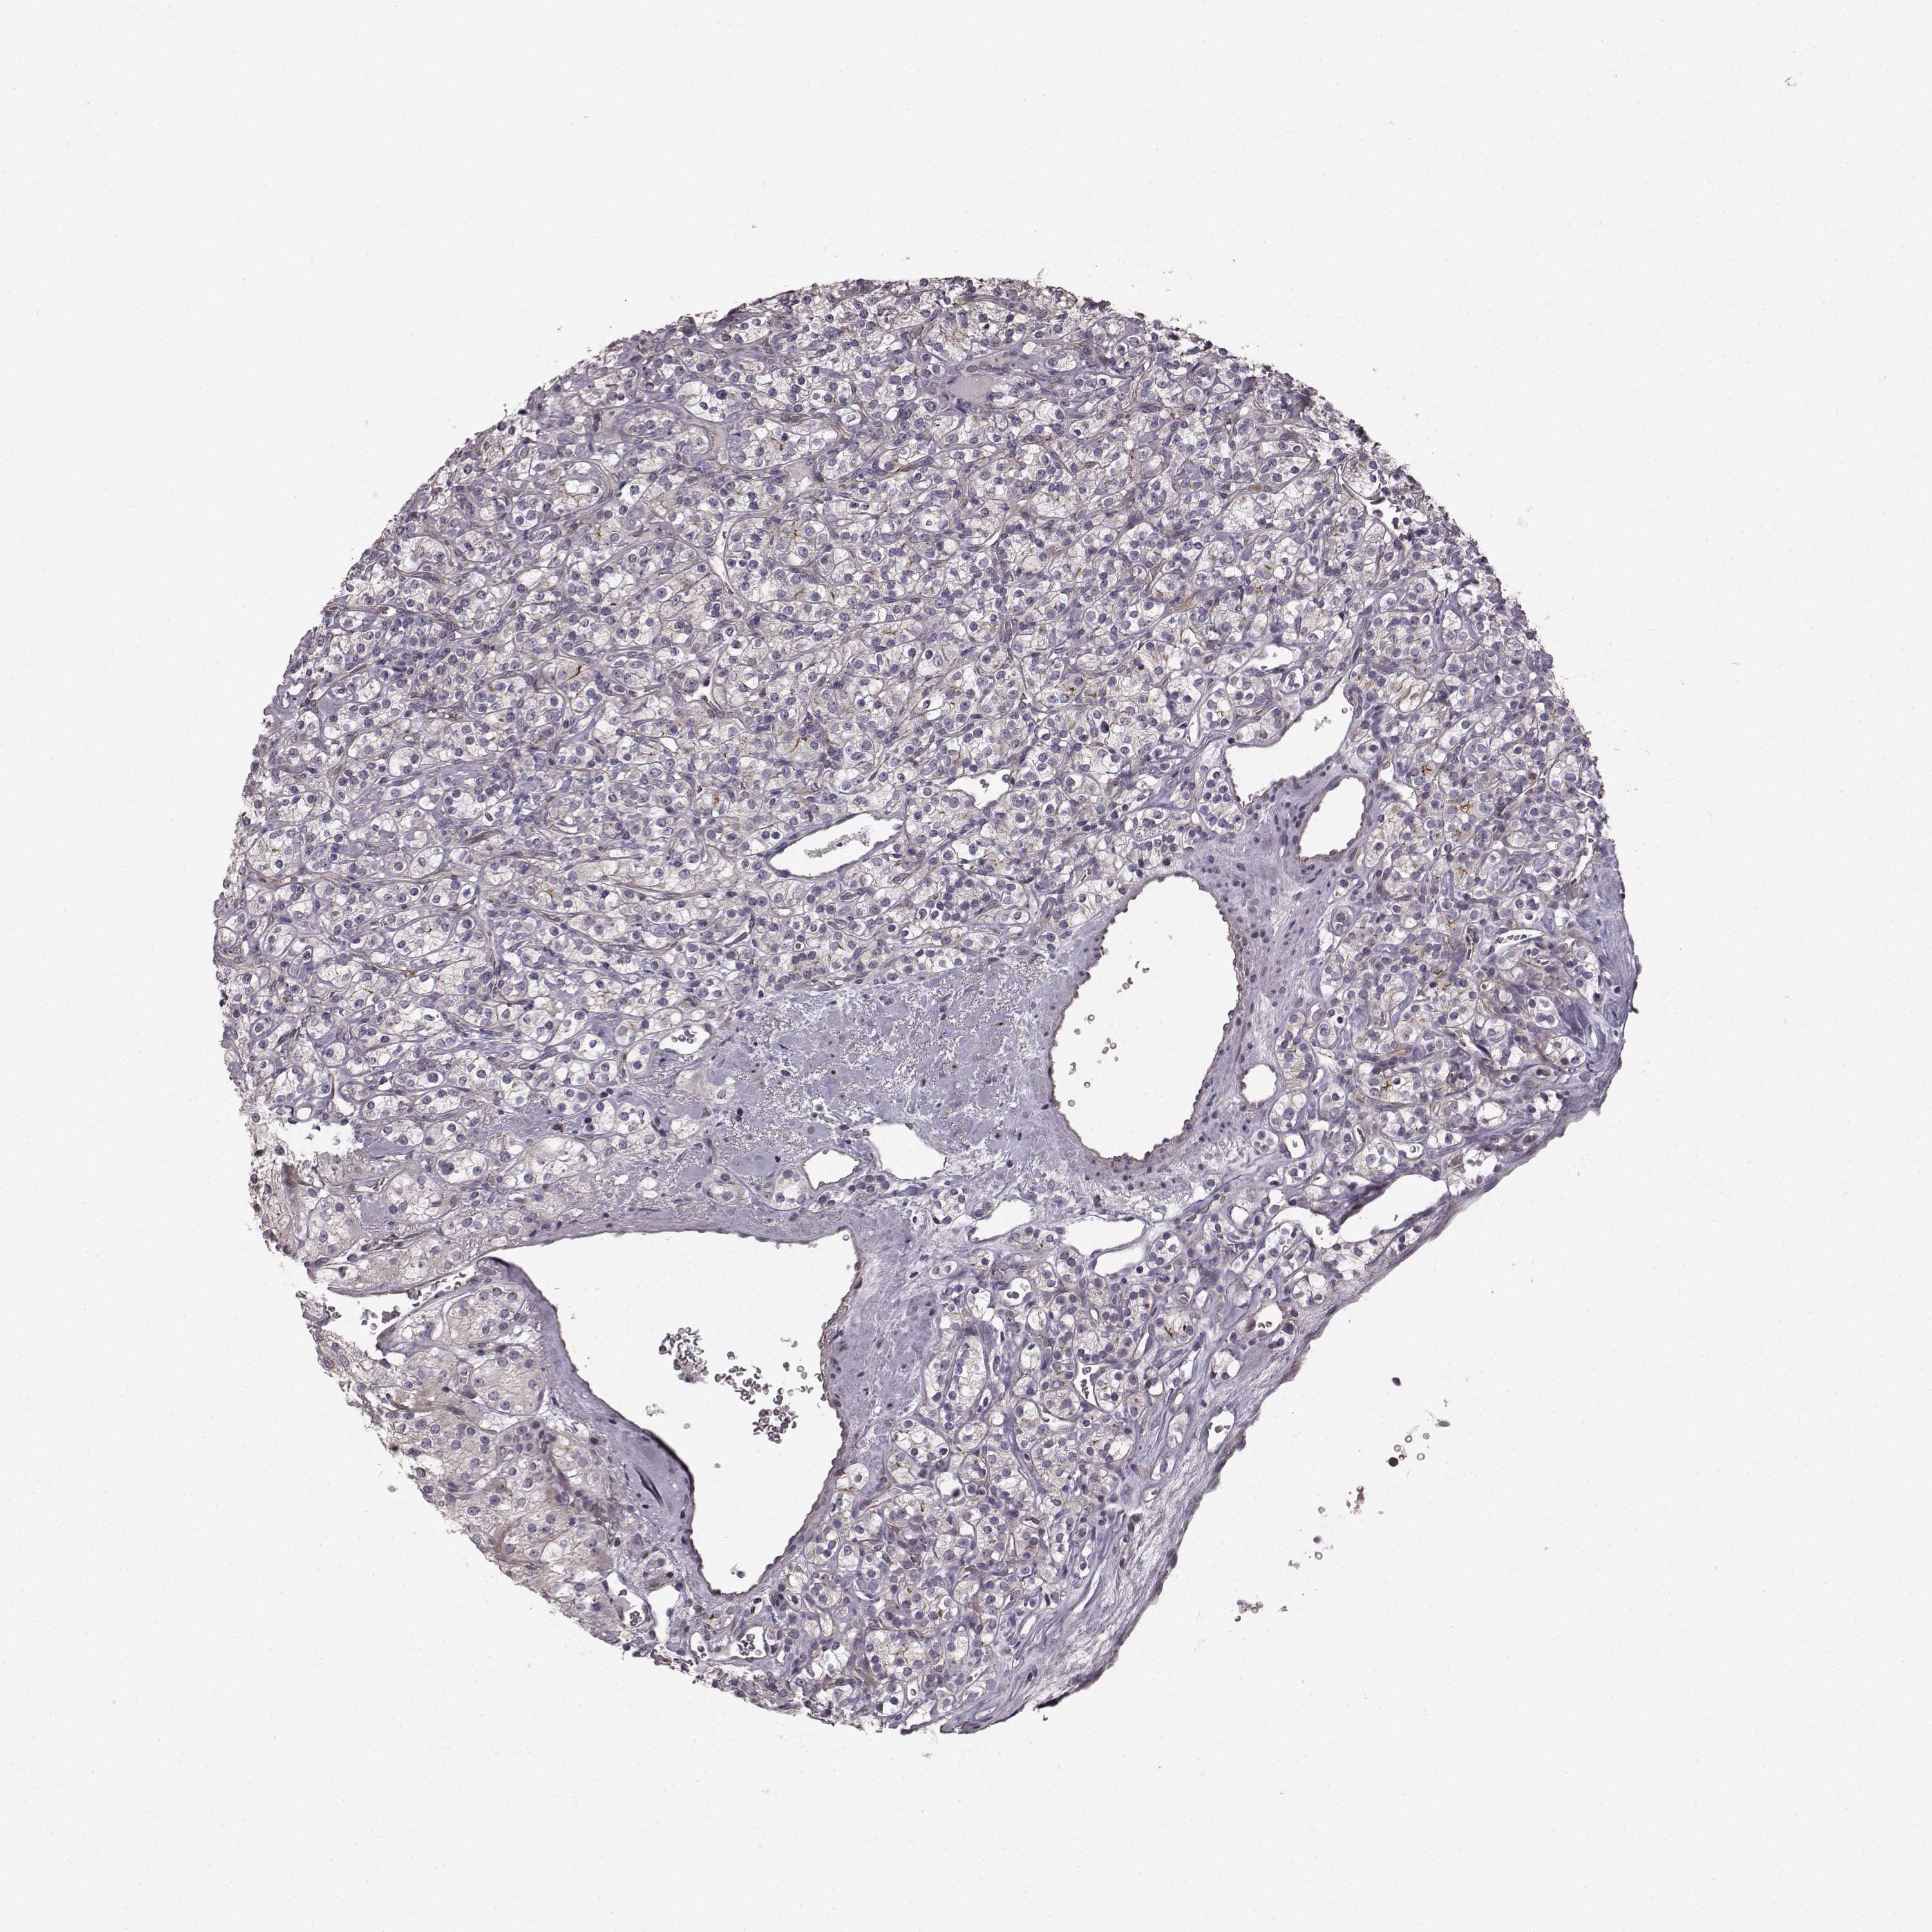

KICH TCGA KIRC TCGA KIRC VALIDATION KIRP TCGA PROTEIN RCC CPTAC PROTEIN EXPRESSION

Renal cancer

Kidney chromophobe

KIDNEY CHROMOPHOBE (TCGA) - Interactive survival scatter ploti

SLC22A18 is not prognostic in Kidney Chromophobe (TCGA)

Average pTPM 13.4

Number of samples 64